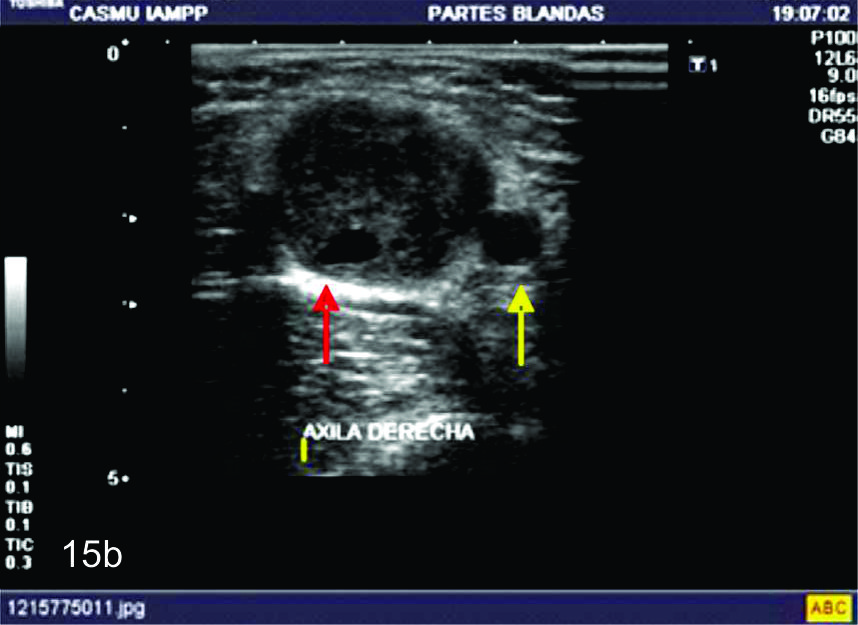

Figura 15

Tumor del nervio cubital a nivel del hueco axilar derecho.

A- SE observa un corte longitudinal del nervio cubital en donde se identifica una lesión sólida, expansiva, fusiforme (marcada entre calipers), la cual se encuentra en continuidad con el nervio cubital (flechas blancas abiertas). B- Corte transversal del mismo paciente en donde se identifica un área quística dentro del tumor, más frecuente en los schwanomas (flecha roja), Flecha amarillaarteria axilar. C- Con el empleo del Doppler de potencia se observa como el tumor se encuentra levemente vascularizado.